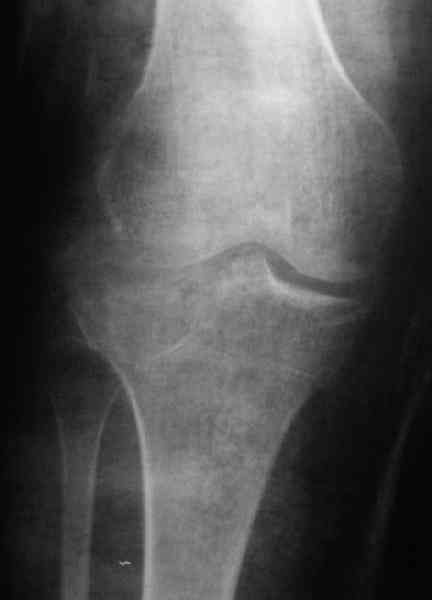

По тактике лечения, более импонирует второй вариант, но наружная плато расколота и туда при нагрузке внедряется н/мышелка бедра, поэтому после дистракции как репонирвать: или стяжными винтами, или изогнутами спицами или субхондральная костная пластика?

Уважаемый Абдурашид. Если нет противопоказаний , то из оперативных способов, я бы рекомендовал следующие: Полное замещение наружного мыщелка аллотрансплантатом либо открытая репозиция с элевацией и замещение дефекта ауто или аллокостью. В Ваших условиях , я бы рекомендовал второй способ. Во-время элевации необходимо разъединить фрагменты со стороны сустава ( надсечь скальпелем по линиям перелома, а затем тонким остеотомом их разъединить. При помощи долота произвести неполную остеотомию ( захватите не менее 1,5 - 2 см губчатой кости и поднять фрагменты, визуально отрепонировать и фиксировать 2-3 спицами. Дефект заместить костным ауто или аллатрансплантатом. Окончательная стабилизация пластиной ( лучше с угловой стабильностью, либо АВФ - позволит спокойно устранить угловую деформацию.